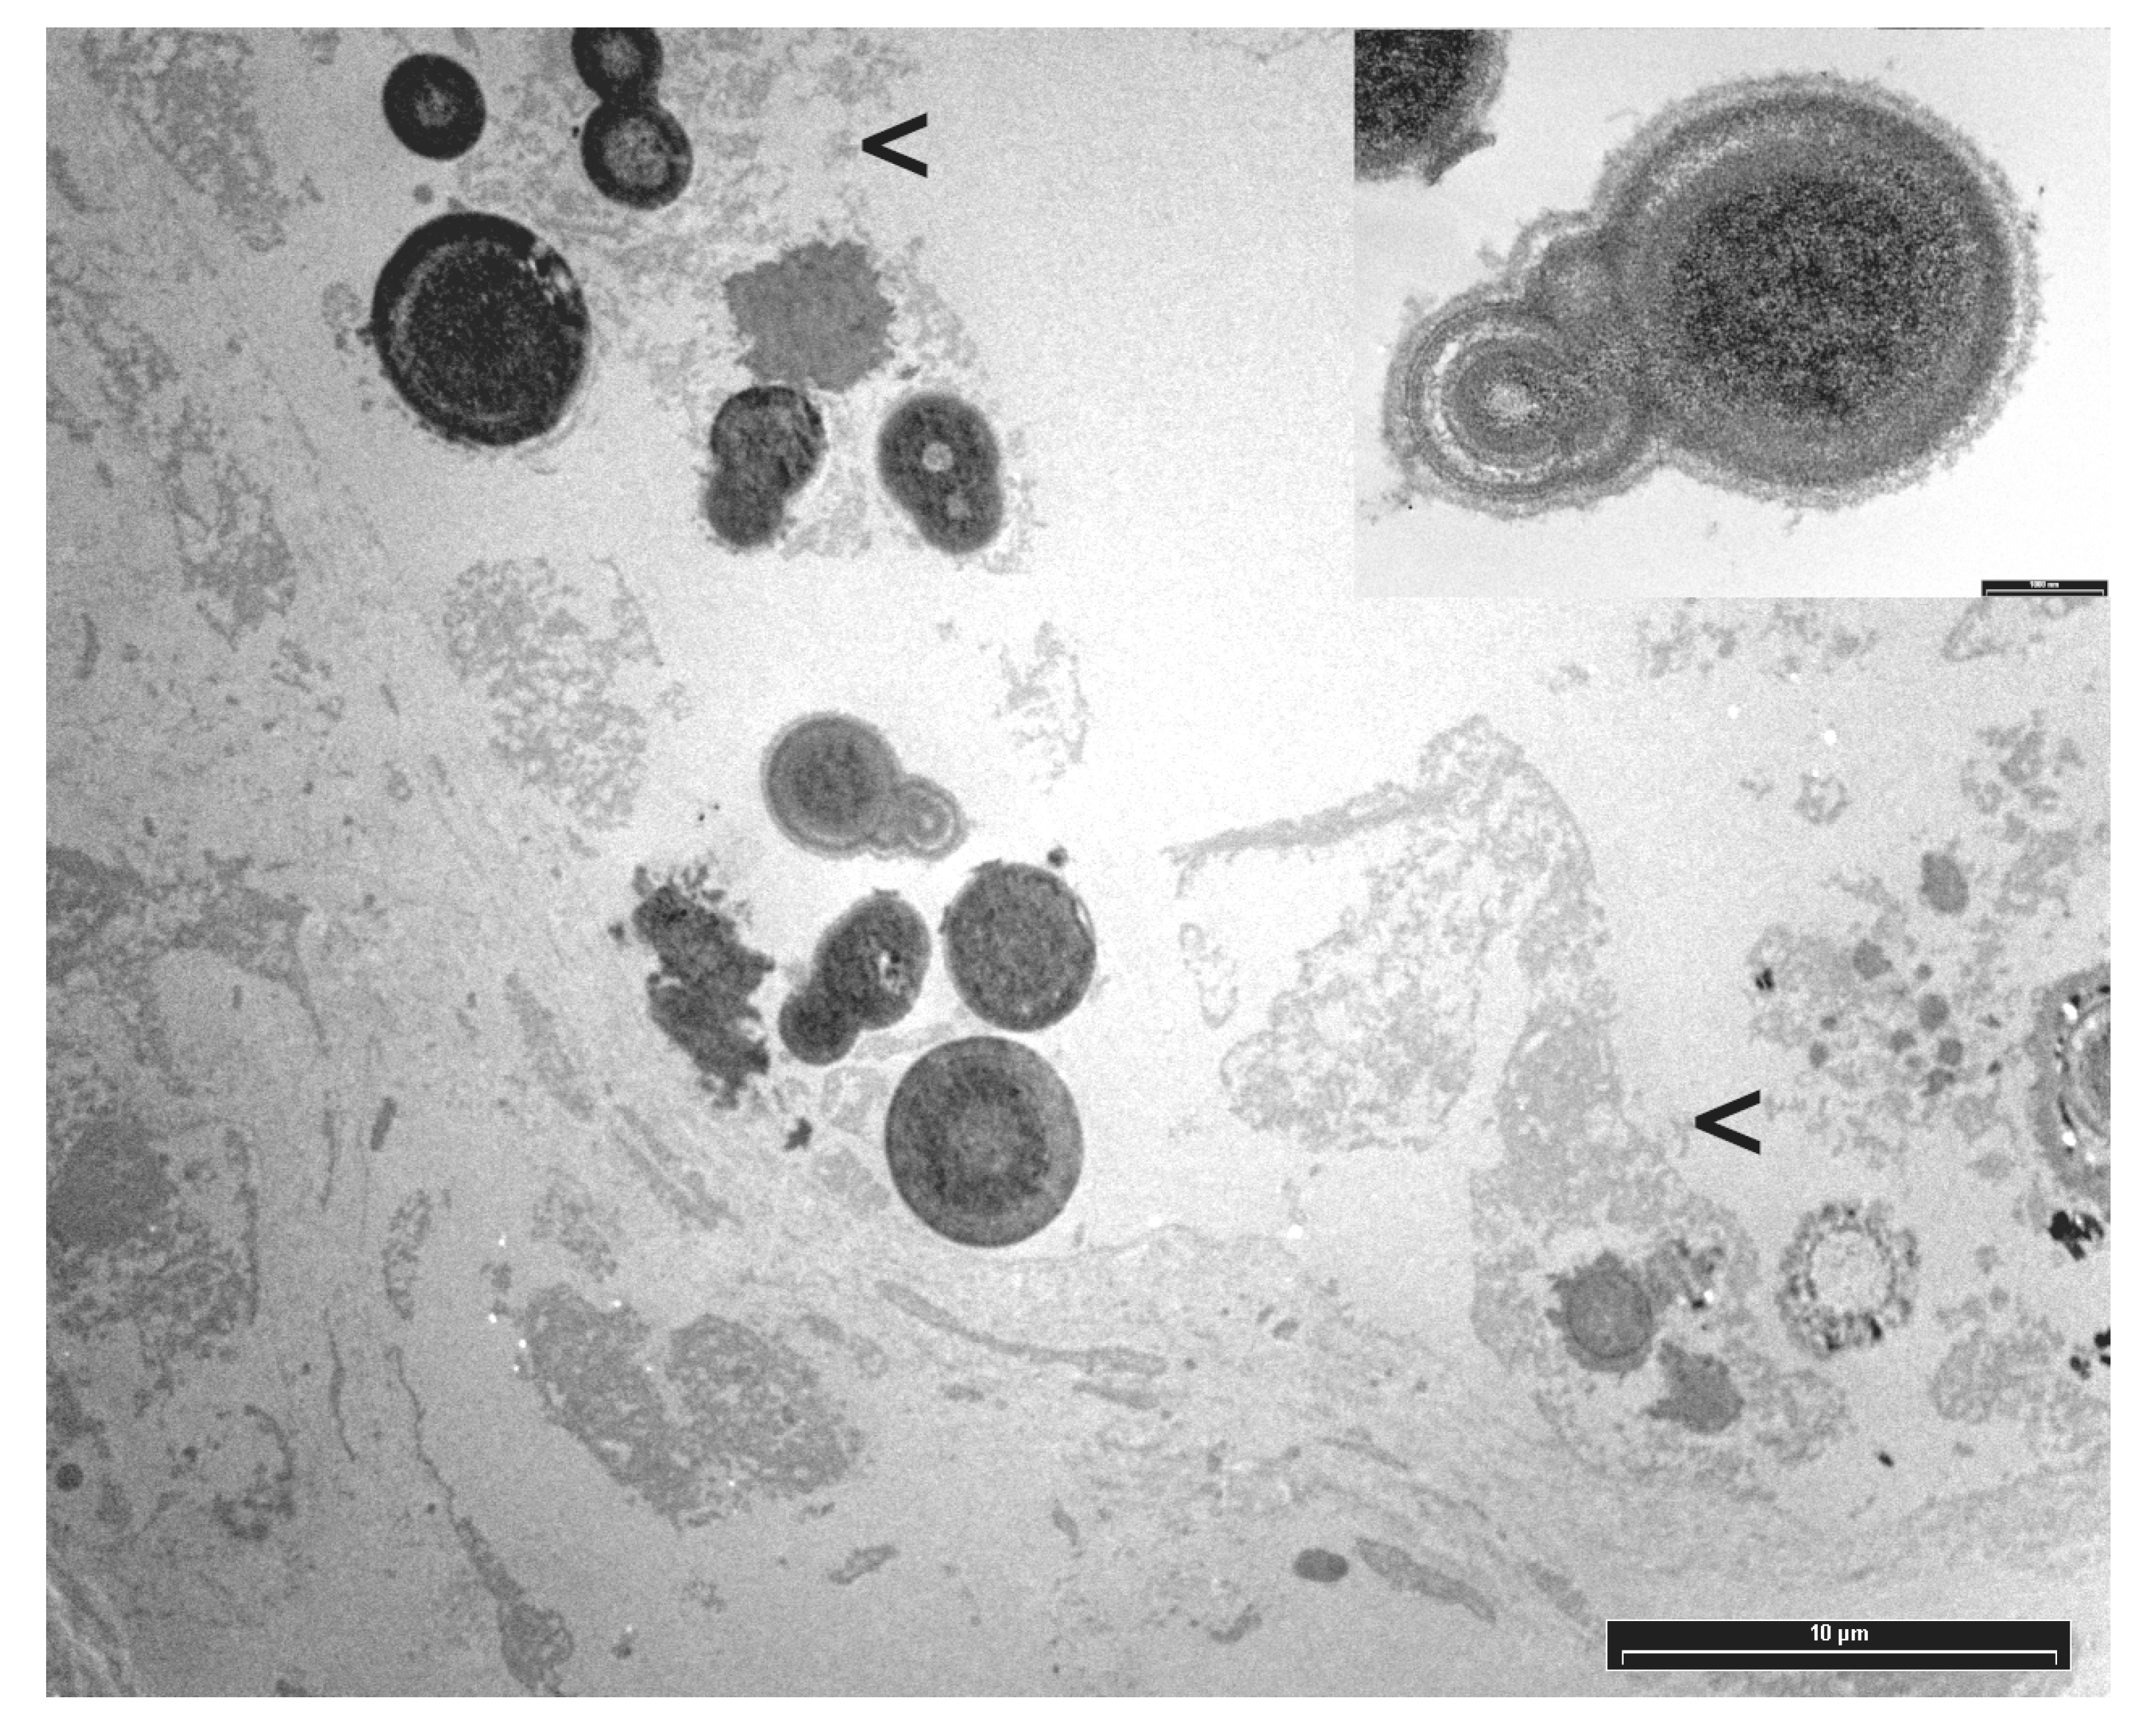

3.3. Electron Microscopy